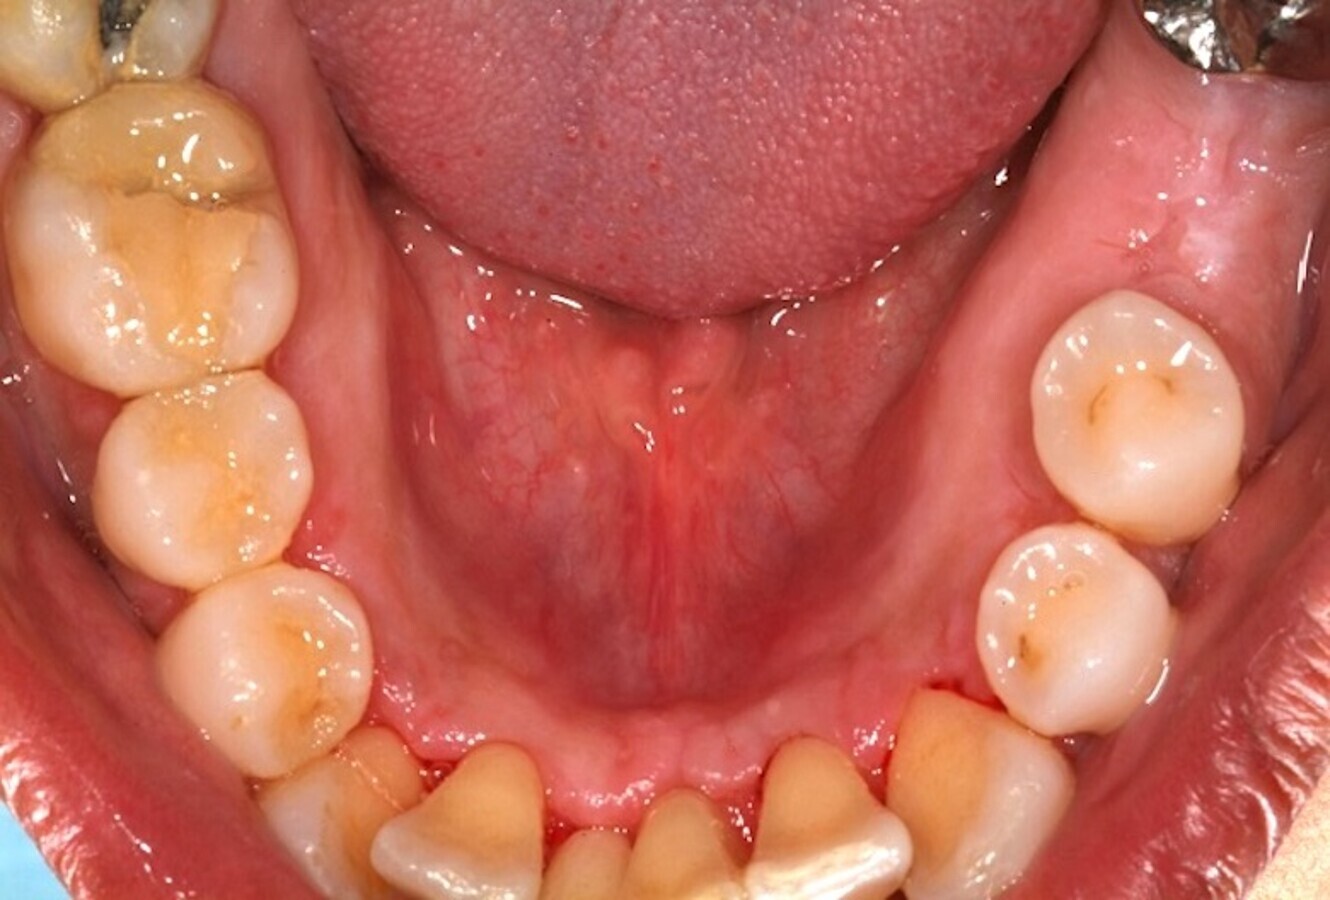

El láser en tejidos duros

Pero la periodoncia no es solo se centra en los tejidos blandos que rodean y dan soporte a los dientes o implantes, sino que también es la “encargada” del tejido duro. Por lo tanto, vamos a abordar brevemente la aplicación del láser en los tejidos duros no dentales.

Algunos láseres como los de erbio, y en mi día a día en concreto el de Er,Cr:YSGG (Waterlase), permiten realizar un corte óseo quirúrgico muy preciso (Figuras 9-13), que transmite un daño térmico mínimo a los tejidos adyacentes9.

El láser Er,Cr:YSGG de alta potencia permite realizar cortes óseos quirúrgicos muy precisos (ver Figuras 9-13).

Figura 9.

Figura 10.

Figura 11.

Figura 12.

Figura 13. Las figuras 9-13 permiten observar un corte óseo quirúrgico muy preciso realizado con láser de erbio que produce un daño térmico mínimo en los tejidos adyacentes.